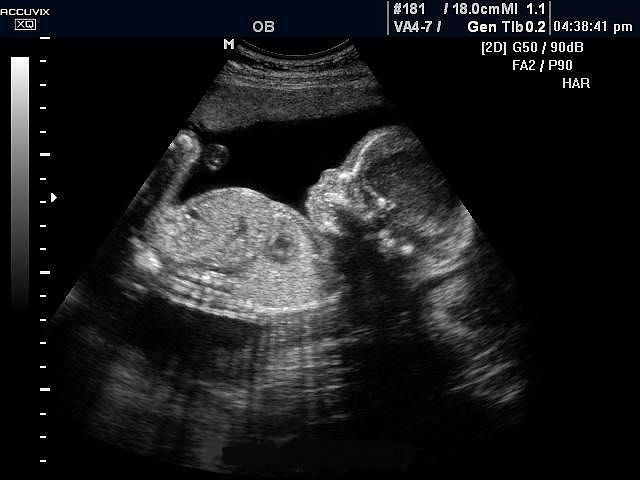

именно чудо..мне когда узи делали в 12 недель ..интерны были и еще пару врачей..короче консилиум... так они все так восхищались и долго рассматривали.. что этот момент мне запомнился больше всего

я тоже когда первый раз в 12 неделек увидела своего сыночка. рыдала..

лучшее, что только можно увидить